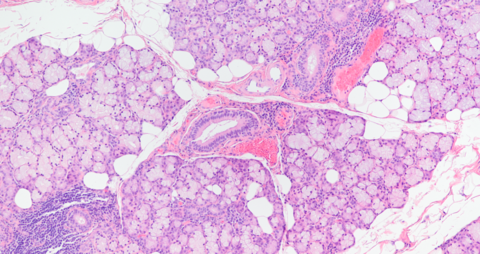

Histopathology

Submandibular gland histologically showing serous-dominant acini consistent with submandibular gland (evaluated in full with no region of mucus-dominant acini as from sublingual gland)

Submandibular Gland 12.5x